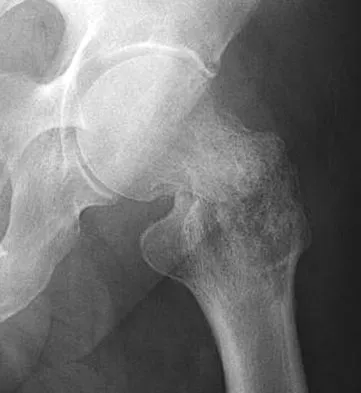

Figures 1a through 1c show the radiograph and MRI scans of a 16-year-old patient who has a painful hip. Examination reveals a significant limp, limited abduction and internal rotation, and severe pain with internal rotation and adduction. A biopsy specimen is shown in Figure 1d. What is the deposited pigment observed in this condition?

Explanation

Pigmented villonodular synovitis (PVNS) is a synovial proliferative disorder that remains a diagnostic difficulty. The most common clinical features are mechanical pain and limited joint motion. On radiographs, the classic finding is often a large lesion, associated with multiple lucencies. Other findings may include a normal radiographic appearance, loss of joint space, osteonecrosis of the femoral head, or acetabular protrusion. MRI is the imaging modality of choice and will show the characteristic findings of a joint effusion, synovial proliferation, and bulging of the hip. The synovial lining has a low signal on T1- and T2-weighted images, secondary to hemosiderin deposition. Copper deposition occurs in patients with Wilson's disease, which mainly affects the liver. Bhimani MA, Wenz JF, Frassica FJ: Pigmented villonodular synovitis: Keys to early diagnosis. Clin Orthop 2001;386:197-202.